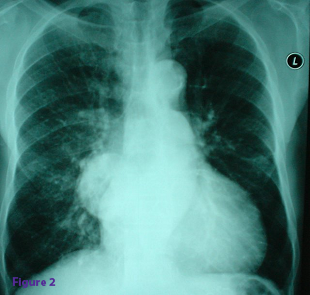

It is uncertain whether this patient also had tendinitis: visceral conditions, including coronary artery disease can occasionally aggravate preexisting musculoskeletal conditions. Therefore, be wary of ending your diagnostic process prematurely when a second condition may be present. Chest films for this patient show a pulmonary mass at the right hilar area (Figure 2).